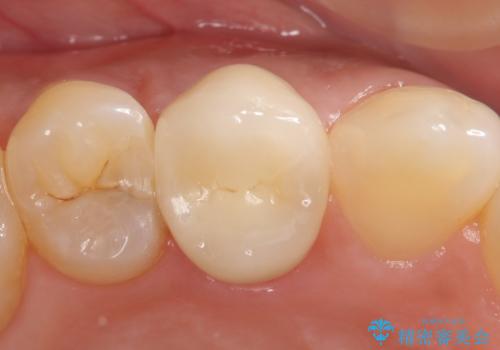

- 右上の歯茎の腫れが引かないので診て欲しいといらっしゃった方の症例です。

検査の結果、右上4番目の歯は神経が死んでおり、そのせいで歯茎に膿の出口が出来ていることがわかりました。

右上4は根管治療を行い、オールセラミッククラウンによる補綴を行いました。